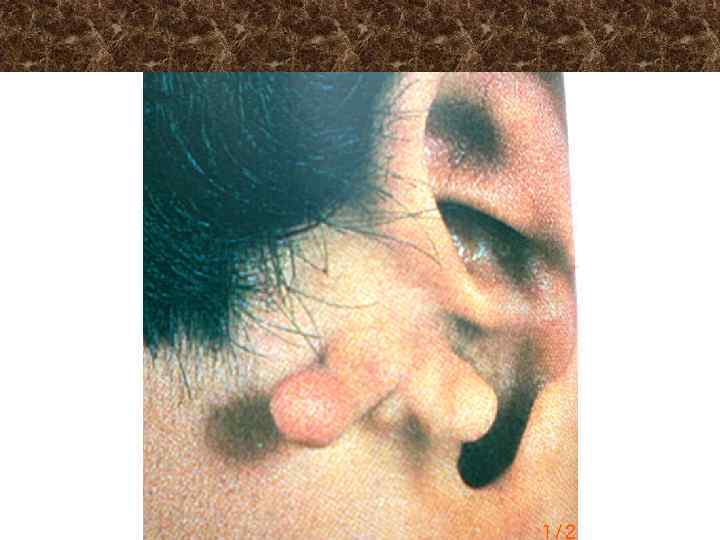

Типичное положение ушной раковины при мастоидите